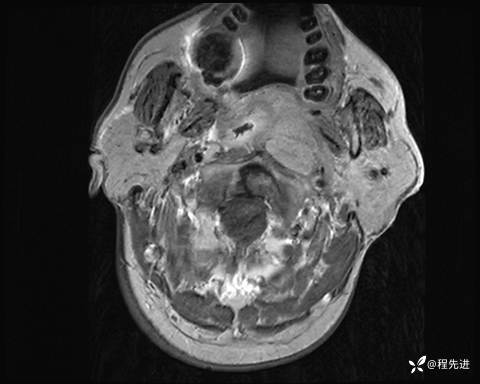

MRI平扫+增强:

T2压脂:

T1:

T1增强: